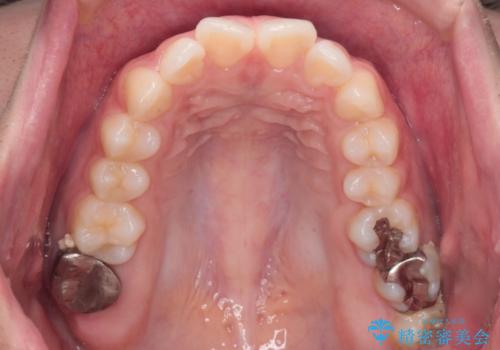

- 前歯が出ていることを主訴に来院された患者様です。

抜歯を希望されなかっため、臼歯部の遠心移動やIPRを行い配列を行っています。

抜歯をしていない矯正となるため、口元に大きな変化は認められません。